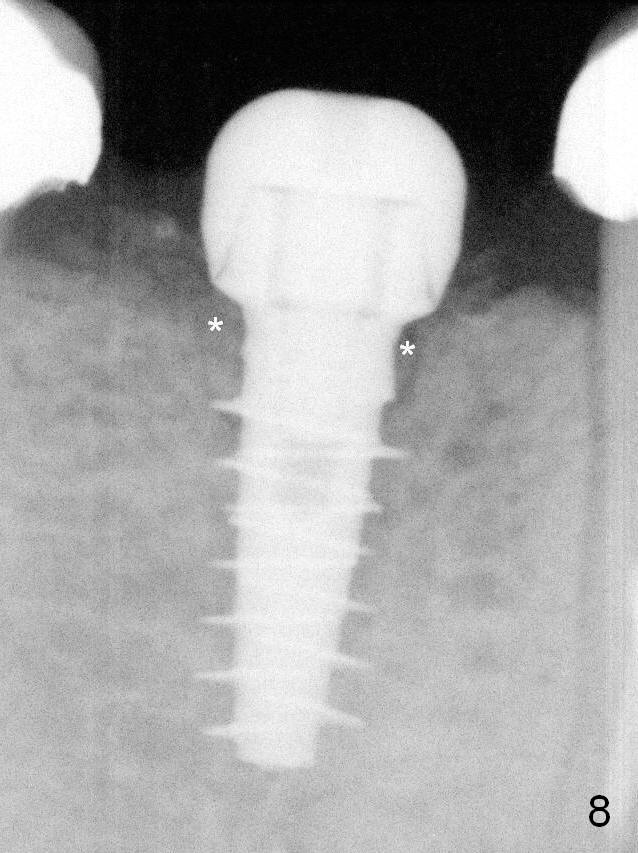

A 4.5x9(1) mm Magicore is placed with 35 Ncm (insertion torque) after 4.3 mm Magic Drill; a 4.5 mm healing abutment is inserted (Fig.7 H).  An error occurs because of using 1 mm cuff of the Magicore.  Ideally 3 or 4 mm cuff should have been used because of reduction in the ridge by ~ 3 mm (Fig.2).  The result of the error is failure of placing the implant at the desirable depth (<9 mm).  The coronal threads are exposed and have to be covered by bone graft (autogenous bone and allograft (.5-1.5 mm) (Fig.8 *), followed by collagen dressing.